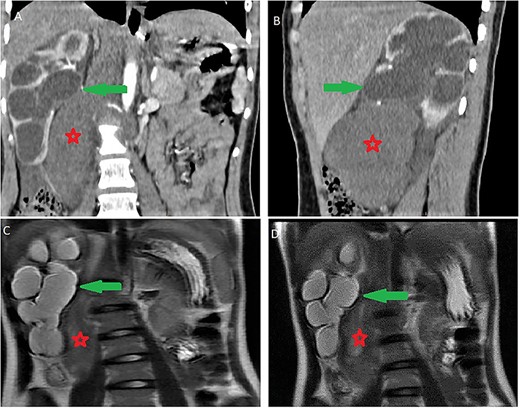

Contrast computed tomography (CT) scan revealed a voluminous (173 × 67 × 59 mm), well-limited and lobulated, right retroperitoneal tumor, hypodense, with delayed and low enhancement (Fig. 1).

Abdominal CT scan showing a retroperitoneal mass; retroperitoneal ganglioneuroma (red spark) before (A) and after (B) heterogeneous enhancement (green arrow).